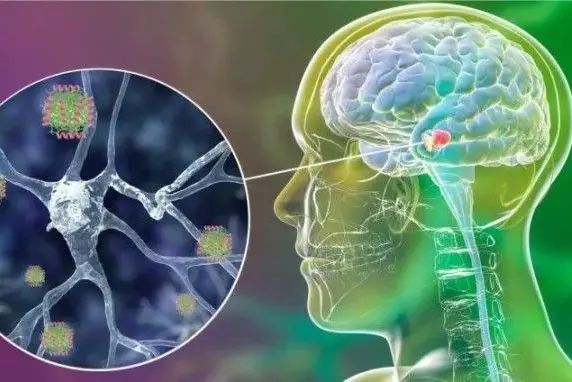

Medical technology innovations bring hope to children with cerebral palsy and autism, giving them a chance to regain health and grow up happily!

Dr. Tian Zengmin, Chief of Neurosurgery and Professor at the Sixth Medical Center of the PLA General Hospital, has devoted over 30 years to the study and treatment of neurological diseases. With extensive clinical experience in treating pediatric brain diseases, Dr. Tian, who is known for his compassion, is now offering free 3-5 minute video consultations for children with neurological conditions (such as cerebral palsy, autism, etc.). This initiative aims to help you understand your child's condition and provide initial treatment guidance, securing a valuable opportunity for your child's health!

Conditions We Treat:cerebral palsy, autism, cerebellar atrophy, epilepsy, intractable epilepsy, cerebral hemorrhage, Parkinson's, Alzheimer's, sequelae of cerebral infarction, and various neurological disorders.